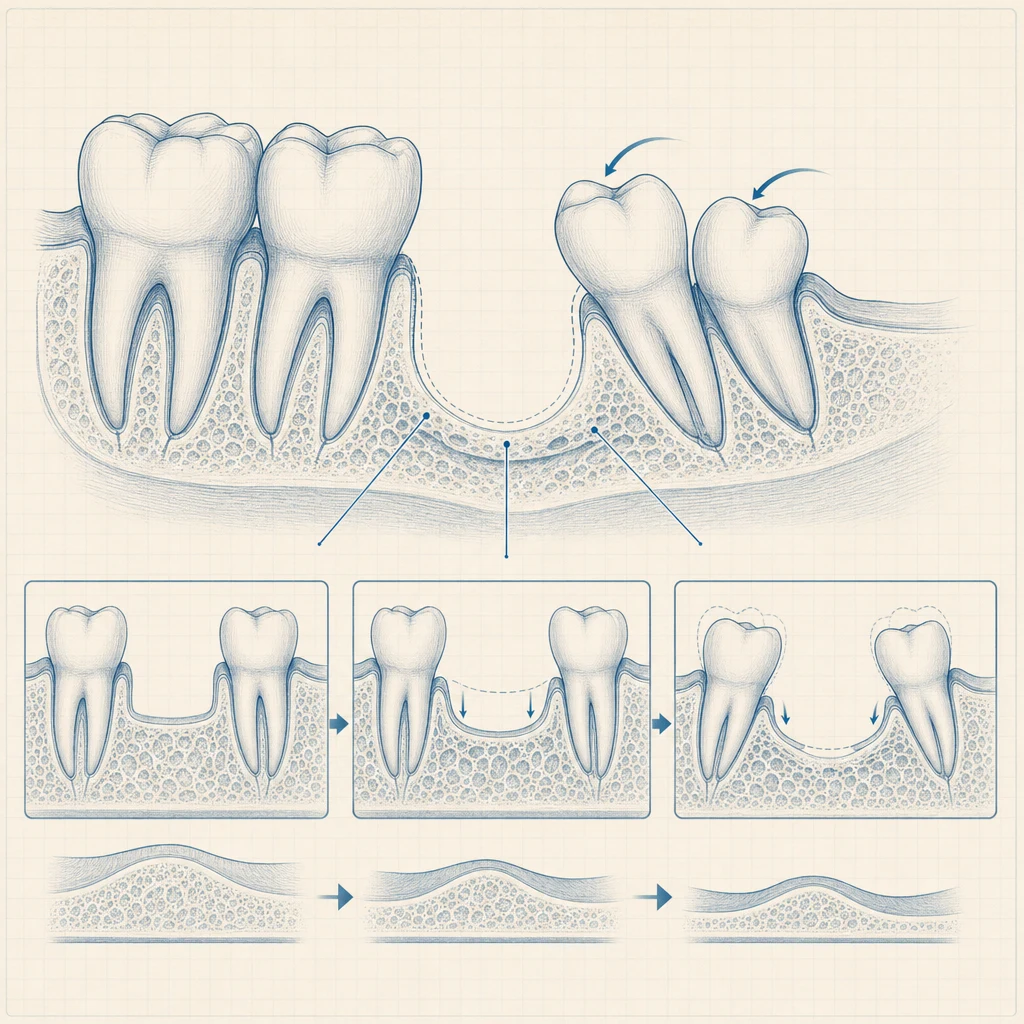

발치 또는 결손치 자리를 그대로 둘 수 없는 이유부터 정리하면:

- 인접 치아의 기울어짐: 빈 공간 쪽으로 옆 치아가 6개월 이내 기울어집니다.

- 대합치 정출: 위·아래 마주보는 치아가 빈 공간으로 솟아오릅니다.

- 잇몸뼈 흡수: 사용하지 않는 치조골은 시간이 지날수록 줄어듭니다.